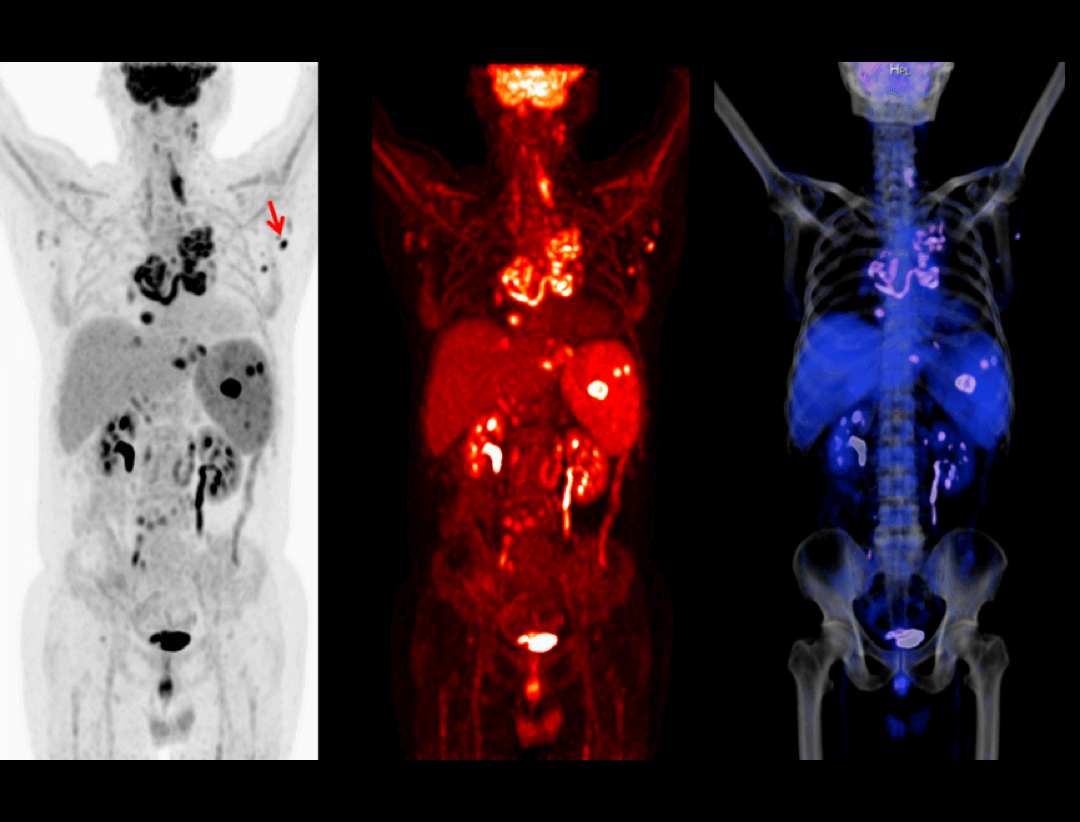

uMI 550搭载自主研发的新一代数字光导探测器,引领PET从「模拟化 」到「数字化 」的时代跨越,系统性能实现多重突破,以超低剂量实现高清成像,大幅提升病灶探测能力;全智能工作流,让临床诊断更精准、更高效、更关爱。

追踪患者随访数据,提供基于PERCIST和RECIST标准的肿瘤评估一站式解决方案